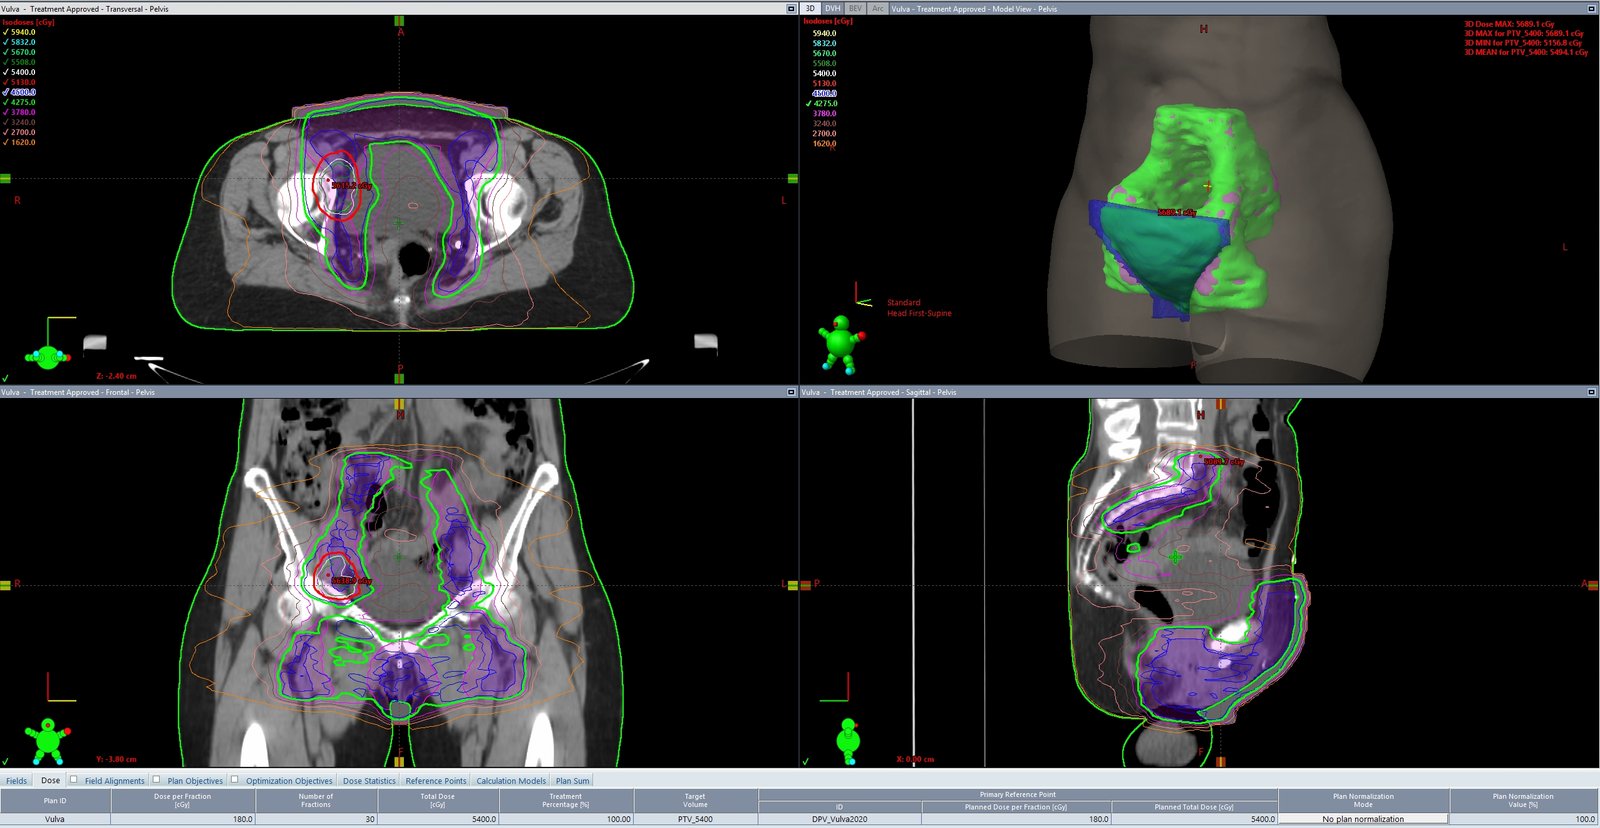

Focusing on larger and more irregularly shaped pelvic target volumes, VMAT provides substantial dose conformity over previously standard three-dimensional radiation treatment planning. This has allowed for radiation dose escalation due to often studied reduced side effects with VMAT technique.